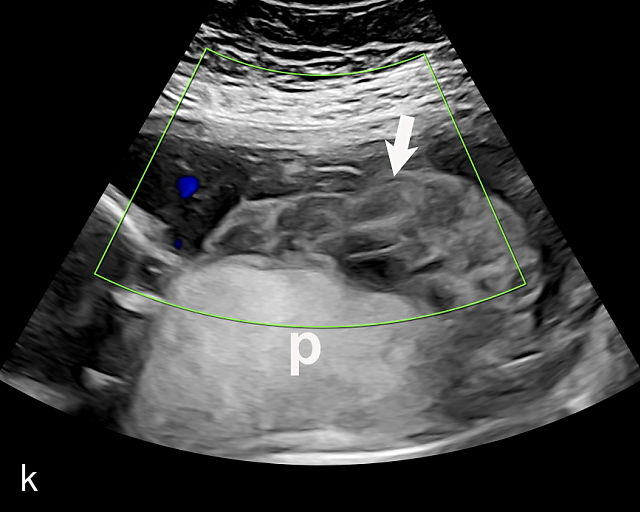

5

Placenta previa and low-lying placenta. (a) Transabdominal grayscale ultrasound image suspicious for placenta previa. The placenta (PL) appears to overlie the internal cervical os (CX). Note the time stamp: 2:19:37. (b) Transvaginal ultrasound of the same patient taken approximately 50 minutes later. Note the time stamp: 3:10:25. The internal os and the lower placental edge are both clearly seen, and the placenta does not overlie the internal os. Because the lower placental edge is 1.93 cm from the internal os, it will likely resolve by the third trimester. (c) Transabdominal grayscale ultrasound of placenta previa. The placenta (p) covers the cervix, but the cervix, especially the internal os, cannot be visualized due to shadowing. (d) Transabdominal grayscale ultrasound of placenta previa. The placenta (p) covers the cervix (c) but shadowing obscures adequate visualization. The internal os is indicated by the arrow. (e) False-positive image of placenta previa on transabdominal grayscale ultrasound. The bladder (b) is full, pushing the anterior and posterior walls of the lower uterine segment (ls) together making it appear that the placenta (p) overlies the internal os of the cervix. In reality, the line depicted by the arrowheads is where the anterior and posterior walls of the lower segment are in proximity to each other. The cervix is much lower and is obscured by shadowing (c). (f) Transabdominal grayscale ultrasound image of placenta previa. The placenta (p) covers the cervix (c), but the cervix, especially the internal os, cannot be visualized due to shadowing. b, bladder. (g) Transvaginal grayscale ultrasound image of placenta previa. The placenta (p) completely covers the internal os (arrow) of the cervix (c). The internal os can be seen clearly. h, fetal head. (h) Transvaginal grayscale ultrasound image of posterior low-lying placenta (p). The lower placental edge is clearly seen and is 1.56 cm from the internal os (arrow) of the cervix (c). The placental edge and the internal os are clearly seen. h, fetal head. (i) Transvaginal grayscale ultrasound image of a posterior placenta previa (p). The internal cervical os is clearly seen (arrow). c, cervix. (j) Transvaginal grayscale ultrasound image of an anterior placenta previa (p). The internal cervical os is clearly seen (arrow). c, cervix; h, fetal head. (k) Transvaginal grayscale ultrasound image of a posterior placenta that was thought to be low-lying on transabdominal sonography but could not be adequately assessed. This examination clearly shows the lower edge of the placenta (p) to be 2.18 cm from the internal os (arrow) of the cervix, firmly establishing that the placenta is not low-lying and allowing the patient to undergo labor safely and deliver vaginally. c, cervix. (l) Transvaginal grayscale ultrasound image of placenta previa. The placenta (p) completely covers the internal os (arrow) of the cervix (c). The internal os can be seen clearly.

This distinction is critical in determining the mode of delivery.49,51 All patients with placenta previa persisting into late pregnancy require cesarean delivery to avoid complications such as severe bleeding.50,60,61 Studies suggest that patients with a lower placental edge located more than 1 cm from the internal os may safely attempt a vaginal delivery without a significant increase in bleeding risk.68,69,70,71

Most cases of placenta previa will be suspected prenatally by transabdominal ultrasound.49 However, this approach has several limitations and may be inaccurate.72,73,74 because the relationship between the placenta and the internal cervical os may be difficult to assess by transabdominal ultrasound.72,73,74 The bladder may be full, pushing the anterior and posterior walls of the lower uterine segment together, falsely creating the impression of a placenta previa (Figure 5e).61 There may be considerable shadowing, including by the fetal presenting part, which may limit the accuracy of transabdominal ultrasound (Figure 5d,f).75 Posterior placentas may be more difficult to assess.

Transvaginal ultrasound overcomes these limitations (Figure 5g–l).72,73,74,76 The probe is inserted into the vagina and therefore is closer to the region of interest.51,61 In addition, transvaginal transducers have higher frequencies and superior resolution compared to transabdominal transducers. Transvaginal ultrasound is safe and is not associated with increased bleeding.72,73,74,75,76 As such, transvaginal ultrasound should be the imaging modality of choice whenever there is suspicion of placenta previa.49,67,77